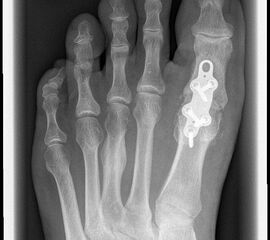

Das nachfolgend präsentierte OP-Verfahren zeigt die Großzehengrundgelenkarthrodese mit Gelenkflächenpräparation mittels sogennanter „Cup-and-Cone“-Fräsen und einer dorsal angebrachten variablen winkelstabilen Platte mit Gleit-/Kompressionsloch.

Durch die Verwendung sogenannter „Cup-and-Cone“-Fräsen und die Osteosynthese mit winkelstabiler Platte ggf. in Kombination mit einer interfragmentären Zugschraube kann die Rate der Pseudarthrosen vor allem bei schlechten Knochenverhältnissen deutlich reduziert werden, sodass dieses Verfahren zunehmend empfohlen wird 9.

Pseudarthrose: Verzögerte Knochenheilung und Pseudarthrosen treten je nach Osteosynthesetechnik unterschiedlich häufig auf. Bei Verwendung von Drähten oder Drahtcerclagen werden hohe Pseudarthroseraten von über 13% beschrieben, daher sollten diese Verfahren verlassen werden1021. Einzelschrauben bieten keine ausreichende Rotationsstabilität und werden daher nur noch selten verwendet. Korrekt eingebrachte gekreuzte Schrauben ergeben zwar bei primärem Hallux rigidus und guter Knochenqulität eine hohe Stabilität, sind jedoch bei osteopenischem Knochen und vor allem bei rheumatoider Arthritis oft unzureichend 141516. Die Rate an Pseudarthrosen kann hier durch Plattenosteosynthese mit interfragmentärer Zugschraube oder mit winkelstabiler Platte mit Gleit-/Kompressionsloch deutlich gesenkt werden 622. Nachteilig ist die Materialstärke der winkelstabilen Platte die zum Teil vermehrt aufträgt und daher gelegentlich die Metallentfernung notwendig macht.